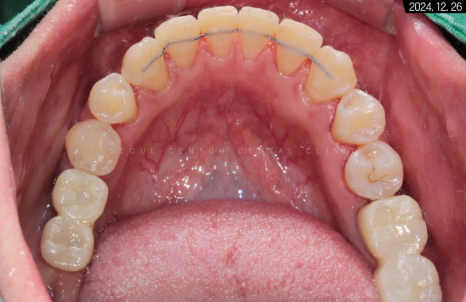

유지장치를 부착하고 난 후의 악궁 사진입니다.

수평 피개가 해소되었기 때문에

측면에서 봐도 중심선이 바릅니다.

둥글게 변하면서

교합 상태가 이상적인 모습을 보이네요.